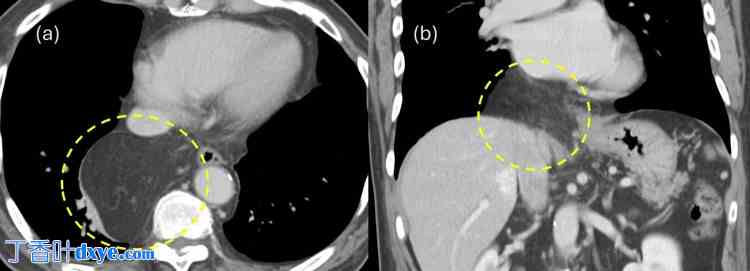

一名79岁的男性患者因胸闷约一个月就诊于当地医院。患者身高169.7 cm,体重70.2 kg。心电图显示心率为65次/分,窦性心律。体格检查未发现胸部和腹部异常。血液检查结果也未发现异常。患者无胃肠道或心血管疾病病史,医生问诊时也未发现腹部或胸部外伤史。然而,患者有糖尿病和血脂异常病史,并定期服药。胸部X光片显示疑似纵隔肿瘤(图1),患者被转诊至呼吸内科。进一步增强MRI(图2)和CT(图3)检查后,由于大网膜血管经食管裂孔延伸至纵隔,怀疑为ITOH,患者被转诊至胃肠外科。患者因症状性疝气接受腹腔镜疝修补术。术中发现食管裂孔右侧为疝口(图 4a),大网膜脱垂至右后纵隔。大网膜未与疝囊粘连,可手法复位至腹腔(图 4b)。

图 1. 胸部 X 光片。

术中发现异常纵隔阴影,怀疑为纵隔肿瘤。